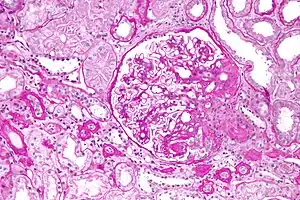

Five mutually exclusive variants of focal segmental glomerulosclerosis may be distinguished by the pathologic findings seen on renal biopsy:[6]

- Collapsing variant

- Glomerular tip lesion variant

- Cellular variant

- Perihilar variant

- Not otherwise specified (NOS) variant.

Recognition of these variants may have prognostic value in individuals with primary focal segmental glomerulosclerosis (i.e. where no underlying cause is identified). The collapsing variant is associated with higher rate of progression to end-stage renal disease, whereas glomerular tip lesion variant has a low rate of progression to end-stage renal disease in most patients. Cellular variant shows similar clinical presentation to collapsing and glomerular tip variant but has intermediate outcomes between these two variants. However, because collapsing and glomerular tip variant show overlapping pathologic features with cellular variant, this intermediate difference in clinical outcomes may reflect a sampling bias in cases of cellular focal segmental glomerulosclerosis (i.e. unsampled collapsing variant or glomerular tip variant). The prognostic significance of perihilar and NOS variants has not yet been determined. The NOS variant is the most common subtype. Collapsing variant is the most common type of glomerulopathy caused by HIV infection.